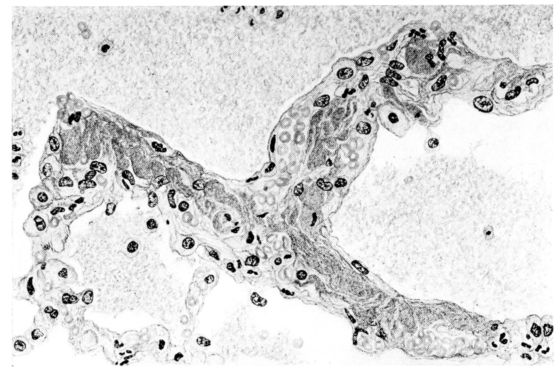

FIG. V. AUTOPSY NO. 95. AN EARLY LESION OF THE BRONCHIOLE CHARACTERIZED BY HYALINIZATION OF THE EPITHELIUM AND SEROUS EXUDATE IN THE LUMEN.

15There is considerable evidence to support the view that the disease spreads from bronchus to bronchus, and in keeping with this view, various stages in the inflammatory processes are more readily determined in these smaller structures than in the trachea. Furthermore, it must be emphasized that even the mildest and the most extreme of these stages are not infrequently encountered in the same lung. The earliest lesion is manifested by an increased homogeneity of the protoplasm of the epithelial lining of the bronchus. The cell protoplasm loses its normal granulation and the nucleus, somewhat darker than usual, becomes conspicuous on a red base (Fig. V). In the lumen of such a tube a serous exudate, perhaps mixed with mucus, is encountered, and there is some spreading apart of the surrounding muscular tissue with engorgement of the vessels. This picture merges gradually into one where the epithelium appears as a homogeneous, red-staining ribbon, devoid of nuclei, often exfoliated, in part at least, from the underlying submucosa (92). The change is traceable through the larger bronchi, even to the ducti alveolares, and not infrequently, bacteria, either as a diffuse, minute dotting or in the form of circumscribed, colony-like formations, are spread through the red, ribbon-like strand (Fig. XVI). With the exfoliation of the epithelial lining, the submucous vessels become more and more conspicuous and may bulge into the lumen of the tube (Fig. VI). That they actually weep into the lumen is proved by the presence of red blood cells in the exudate, now rich in mucus, broken-down nuclei, and desquamated cells. The necrotizing process may not extend deeper than the epithelial lining as is the status described above (140, 162), but it also frequently involves the underlying submucous and muscular layers, so that these lose their identity and stand out as homogeneous masses, in which fragmented nuclei and bacterial accumulations are prominent. Such deeper necrotizing areas may be focal (Fig. VII), or may involve the entire circumference of the tube (Fig. VIII). Occasionally, the epithelium, now dead and staining homogeneously, is lifted from the underlying submucosa in the form of a blister (66), and has very much the same appearance as the well known, early reaction which follows the application of croton oil to the rabbit’s ear. Where this occurs, the submucosa is less involved, as though the necrotizing agent had not penetrated to the same depth and the serous reaction beneath were actually a beneficent exudate. These blisters are in contrast with the deeper areas where the fibrinous mass, mixed with the dead tissue, forms an intensely staining ring or band, which extends through the bronchiolar wall even to the surrounding alveoli.

A more striking picture, however, even than this aplastic alveolar exudate appears in the terminal bronchioles. In many instances, these are conspicuous on account of their size, for they are dilated to form prominent, often irregular, sacs (Fig. XV). The distention of these terminal bronchioles may be so great that the surrounding alveoli are compressed. What makes them even more conspicuous is their lining, once epithelium, but now a swollen, thick, homogeneously staining material, with complete loss of architecture; the material forms (with hematoxylin and eosin) a red band limiting the lung tissue and sharply demarcating it from the exudate within the bronchioles (48, 92). However, this ribbon of red, often thickened by fibrin deposition, is not always pure, for bacteria thrive in the dead tissue. They occur singly, paired, in chains, and also as circumscribed, dense masses which in size and position, simulate nuclei (162) (Fig. XVI). This same hyalinization of the epithelium, it will be recalled, occurs in the larger bronchi (Fig. V), and there, too, bacteria frequently develop in the dead tissue (Fig. VIII). In the smallest bronchiolar ramifications, acute epithelial necrosis is not infrequently encountered, even when the surrounding lung tissue is relatively normal (Fig. XVI). That the process does not stop with the epithelium, but, as in the larger bronchi, may extend through the entire structure of the bronchioles, is manifest. Even the alveolar walls may be involved and frequently homogeneous pink or red bands, now the phantom of the former viable lung tissue, mark the presence of the old wall of the alveolus (Fig. XVII). Occasionally, some architecture remains in this pink ribbon and then the involvement seems to be primarily in the vessels of the wall. Not all the vessels are involved, and next to a hyaline thrombus in one, there may be fresh blood, usually red blood, in its neighbor. The alveolar epithelium is usually denuded and thus accentuates the intensity of the change.